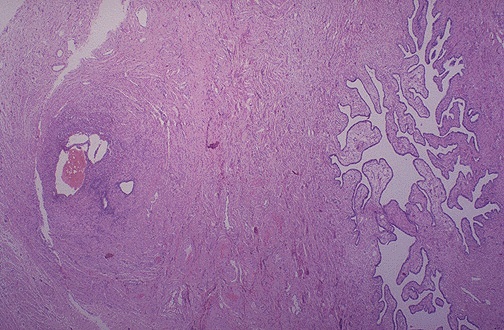

Here, a small cluster of endometrial glands and stroma with hemorrhage are seen at the left near the surface of the fallopian tube. The lumen of the tube is at the right. This is a focus of endometriosis.